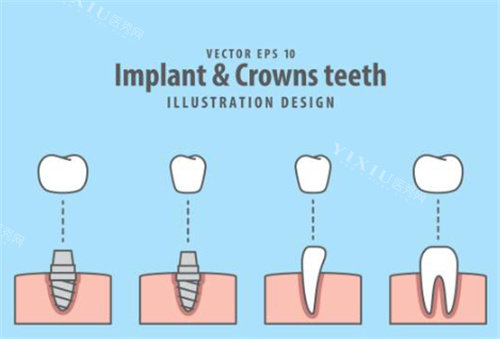

根据查询结果显示,高娅口腔确实具备合法执业资质,诊所登记类别为口腔专科门诊部,执业范围包括牙体牙髓病、牙周病、口腔修复等常规诊疗项目。

高娅医生:诊所研究人,毕业于重庆医学大学口腔医学校,从事口腔临床工作15年,擅长种植牙和美学修复。

病例1:种植牙体验

王女士(35岁)分享:

"在高娅口腔做了前牙种植,整个过程很可靠。术前做了详细检查,医生给出了三种方案让我选择。然后选择了瑞士ITI种植体,手术过程比想象中轻松,术后修复也很不错。现在已经用了2年,没有任何不适。"

全瓷冠:2000-4000元/颗

种植牙:8000-15000元/颗